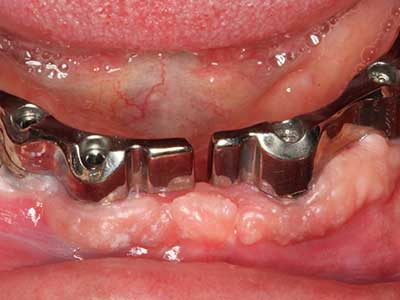

Fig. 16: También condiciones intraorales estables con incorporación de los implantes en la encía queratinizada.

Fig. 17: Tomografía computarizada de un osteoma de crecimiento progresivo ...

Fig. 13: En este paciente de 52 años con una anchura del hueso residual del maxilar inferior de 4 mm, hay que asegurarse de que exista refrigeración por agua adecuada durante la partición del hueso.

Fig. 14: Incorporación de cuatro implantes RSX cónicos (Bego Implant Systems, Bremen).